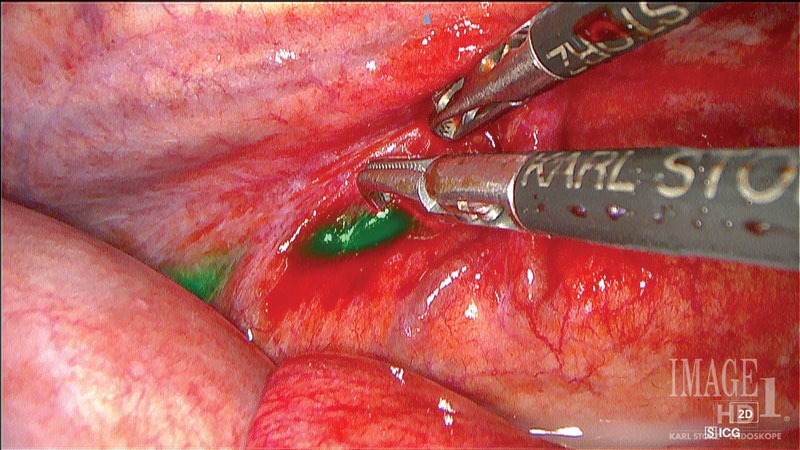

Although pre-operative imaging is useful in approach planning, the thoracic duct itself is not readily visualized intra-operatively. Advances in methods for visualizing the thoracic duct intraoperatively have occurred over the past decade.24,25 Traditionally, methylene blue was used for visualization of the thoracic duct.26,27 Many different injection sites have been described, such as the popliteal lymph node, diaphragmatic crus, intra-hepatic, or cecocolic lymph node. Recently, using indocyanine green (ICG) for direct near-infrared fluorescence lymphography (NIRF-L) has flourished for a variety of purposes. The use of ICG for visualization of the thoracic duct has been described with better visualization than methylene blue (Figure 8).23

Figure 8. View of the thoracic duct of the same dog pictured in Figure 6, now well highlighted with the use of ICG and NIFR. Photo courtesy Dr. Ashley Villatoro